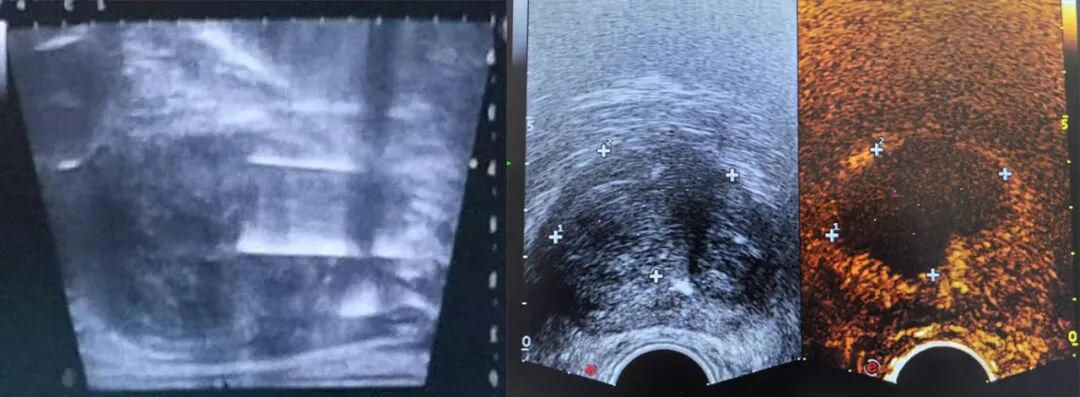

患者前列腺肿瘤位于右侧尖部,在手术室行纳米刀肿瘤消融术,术前常规消毒铺巾,麻醉科协助为患者进行气管插管全身麻醉。术中患者取仰卧位,田晶教授在超声引导下定位病灶并经会阴穿刺,共进4根针开始消融。消融过程中电流上升反馈良好,无不良反应。即刻消融区域造影下可见明显,覆盖全部病变区域。术后复查影像显示病灶消融界限明显,消融效果良好。